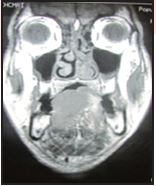

MRI of the tongue